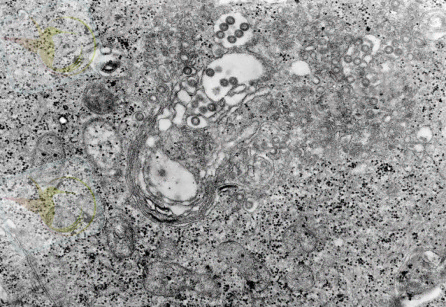

Бұл көптеген жедел жұқпалы аурулар тобы, осыларды біріктіретіні вирусты этиологиялығы, табиғи ошақтығы, айқын капиллярдың эндотелиінің зақымдалуы, геморрагиялық синдромының дамуы.

Вирус денеге кене шаққанда тері арқылы түседі. Вирустың тропизмдік қасиеті гипоталамикалық ортаға және вазотроптік (зақымдайды бүйрек, бауыр және ОЖЖ ұсақ тамырларының эндотелиін) . Осының нәтижесінде қантамырлардың өткізгіштігі жоғарылайды, қанның ұю жүйесінің қызметі бұзылады «ТІШҚҰң- дамиды. Сонымен қатар сүйек миының клеткаларының өсуі басылады, бауырдың функциясы бұзылады.